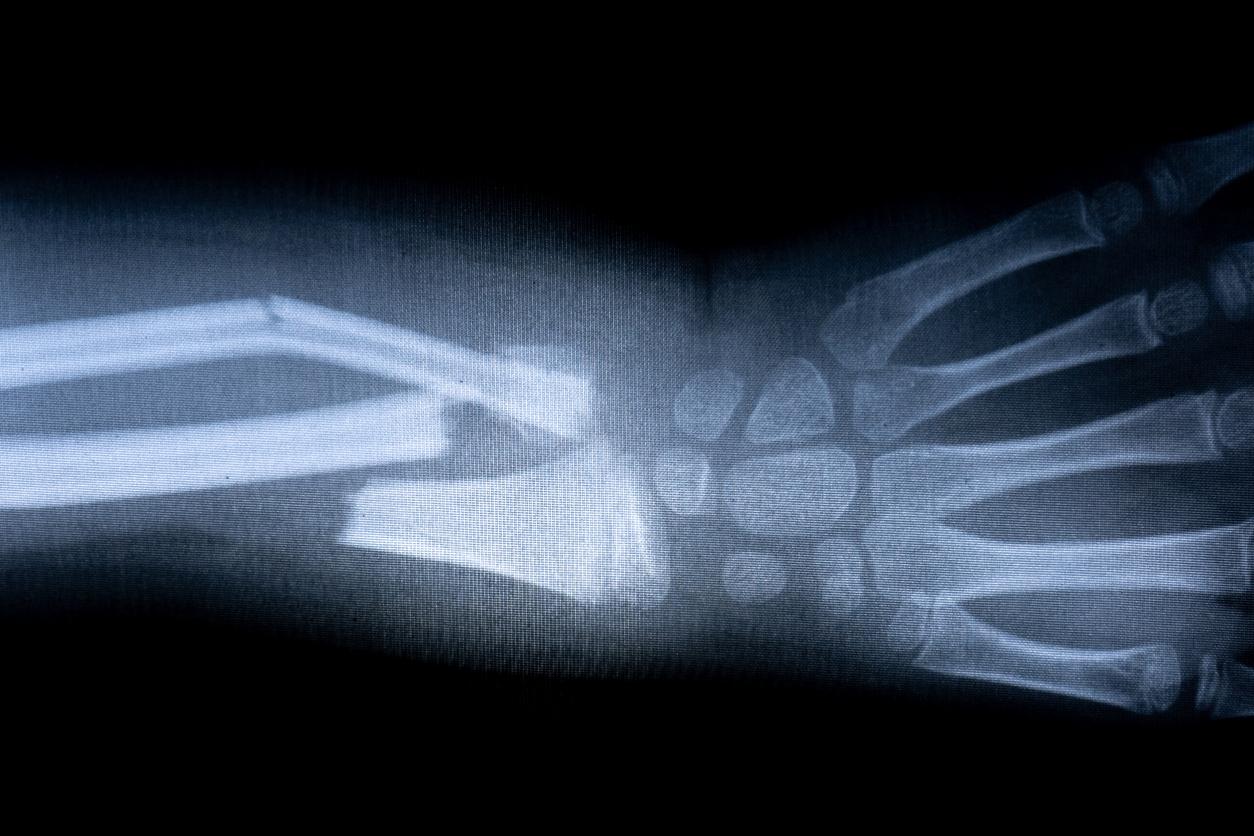

Selon une nouvelle étude publiée dans Radiology, le nouveau système d'intelligence artificielle BoneView® peut apporter une aide précieuse aux urgentistes et aux radiologues lorsqu’ils diagnostiquent des fractures.

Avant le début de l’étude, le système d'IA BoneView® a été entraîné sur 60 170 radiographies obtenues chez des patients ayant subi un traumatisme. Puis, entre 2016 et 2018, 600 adultes chez qui des radiographies avaient été obtenues après un traumatisme récent (avec ou sans une ou plusieurs fractures de l'épaule, bras, mains, bassin, jambe ou pied) ont ensuite été inclus dans une cohorte. Six radiologues et six médecins urgentistes ont alors été invités à détecter et à localiser les fractures avec et sans l'aide du logiciel BoneView®. La sensibilité, la spécificité et les temps de lecture avec et sans aide ont été comparés après calcul de la moyenne des performances de chaque lecteur.

Bilan : l'aide de l'intelligence artificielle a amélioré la sensibilité des médecins de 12% pour les fractures uniques et de 22% pour les patients présentant plusieurs fractures. L'intelligence artificielle a aussi réduit le nombre moyen de faux positifs par patient sans fracture de 42%.